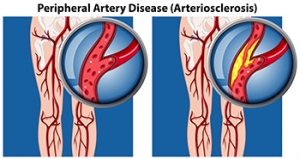

Peripheral arterial disease (PAD) occurs when the outer, or peripheral, arteries narrow due to a build-up of plaque. Peripheral arteries transport blood—which carries oxygen and nutrients—to the legs and arms, keeping the skin and underlying tissue alive and healthy. When PAD is present in the legs, it can reduce the normal amount of blood flow, oxygen, and nutrients to the feet. This may lead to dysfunction in the skin and tissue, causing it to break down and make it more susceptible to developing wounds. PAD can be an inherited disease, or may be caused by diabetes, hypertension, high cholesterol, or obesity. Symptoms of PAD in the feet may include burning, aching, coolness, redness, reoccurring infections, and sores in the toes and feet that do not heal. If you are experiencing any of these symptoms, contact a podiatrist for a full examination, testing, diagnosis and proper treatment.

Peripheral artery disease (PAD) is when arteries are constricted due to plaque (fatty deposits) build-up. This results in less blood flow to the legs and other extremities. The main cause of PAD is atherosclerosis, in which plaque builds up in the arteries.

Symptoms

Symptoms of PAD include:

- Claudication (leg pain from walking)

- Numbness in legs

- Decrease in growth of leg hair and toenails

- Paleness of the skin

- Erectile dysfunction

- Sores and wounds on legs and feet that won’t heal

- Coldness in one leg

It is important to note that a majority of individuals never show any symptoms of PAD.

Diagnosis

While PAD occurs in the legs and arteries, Podiatrists can diagnose PAD. Podiatrists utilize a test called an ankle-brachial index (ABI). An ABI test compares blood pressure in your arm to you ankle to see if any abnormality occurs. Ultrasound and imaging devices may also be used.

Treatment

Fortunately, lifestyle changes such as maintaining a healthy diet, exercising, managing cholesterol and blood sugar levels, and quitting smoking, can all treat PAD. Medications that prevent clots from occurring can be prescribed. Finally, in some cases, surgery may be recommended.